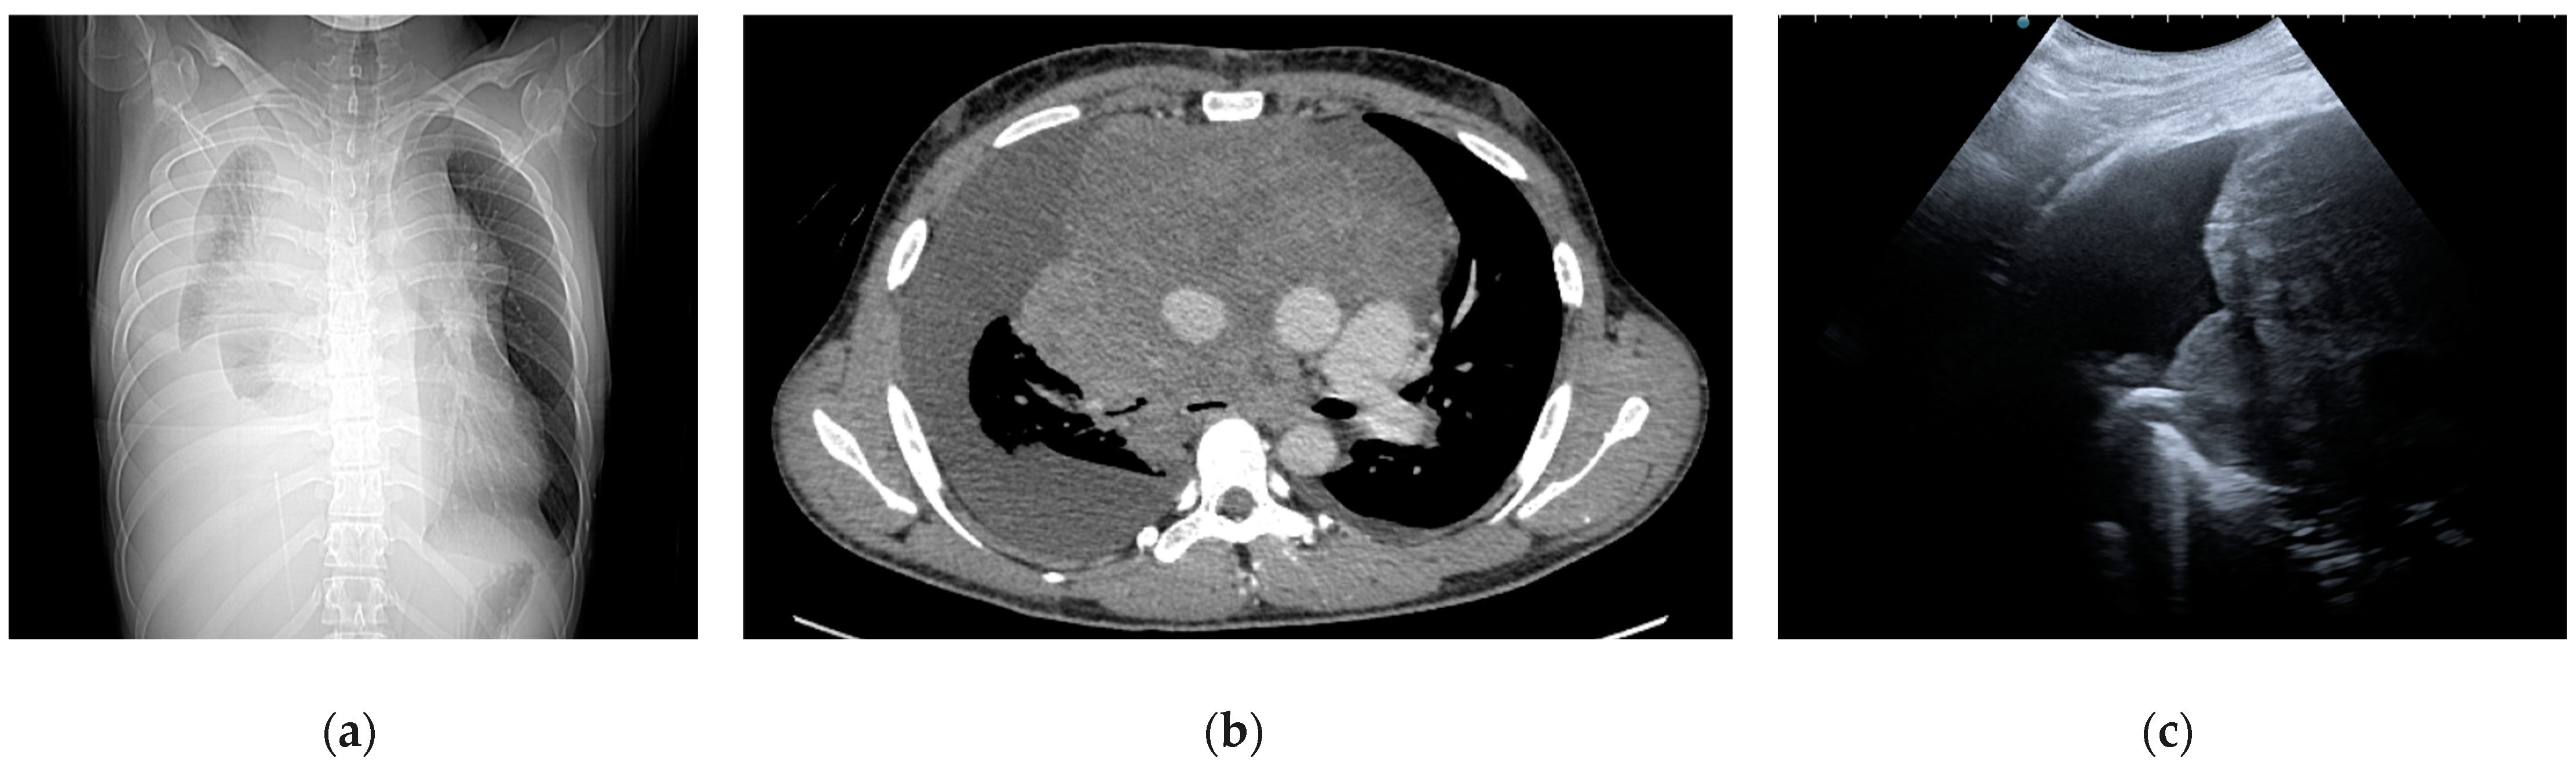

5.1. Transcutaneous Mediastinal Ultrasound (TMUS)

5.3. Computed Tomography (CT)

4.2. Endoscopic Ultrasound (EUS)